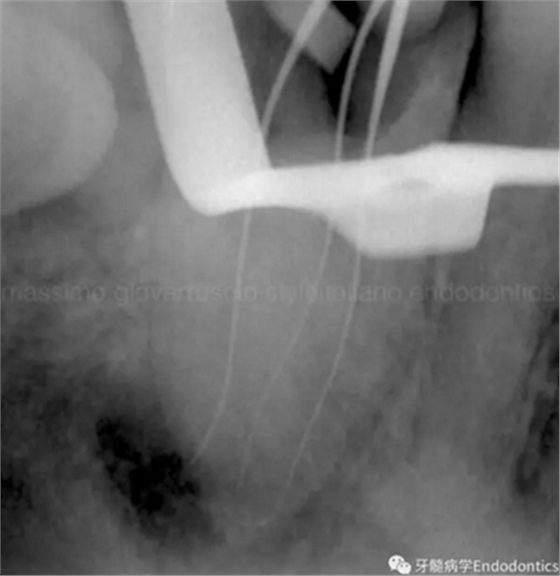

圖1.探查冠方2/3可以獲得有關(guān)根管系統(tǒng)解剖形態(tài)的相關(guān)信息,獲得根管彎曲和多重彎曲程度,或者是否存在根管彎曲的一些重要反饋。醫(yī)生需要重視五種可能遇到的根管解剖類型(包括融合、彎曲、多重彎曲、分歧、分支)。

當(dāng)建立直線通路、找到所有的根管口后,重心應(yīng)轉(zhuǎn)移到根管預(yù)備上。若牙髓存在活力且持續(xù)滲血,應(yīng)使髓室內(nèi)充滿粘性螯合劑。在牙髓已壞死的情況下,應(yīng)使用加熱的5.25%次氯酸鈉溶液沖洗并徹底充滿髓室。探查前,根據(jù)術(shù)前X線片測量并預(yù)彎小的不銹鋼銼,以順應(yīng)預(yù)估的根管長度及彎曲度。使用0.02錐度的10號不銹鋼手用K銼探查根管冠方2/3。